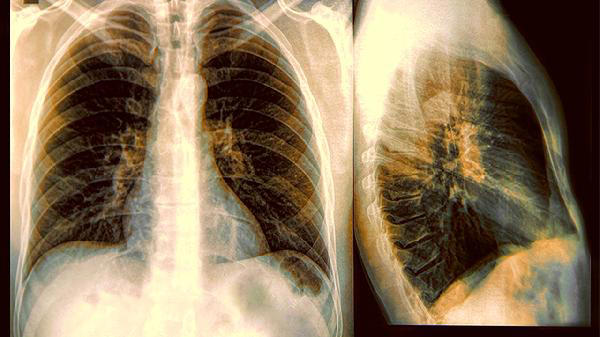

1、定期体检很关键

常规体检中的胸片检查虽然能发现部分问题,但对于早期病变检出率有限。高危人群可以考虑更精确的检查手段。